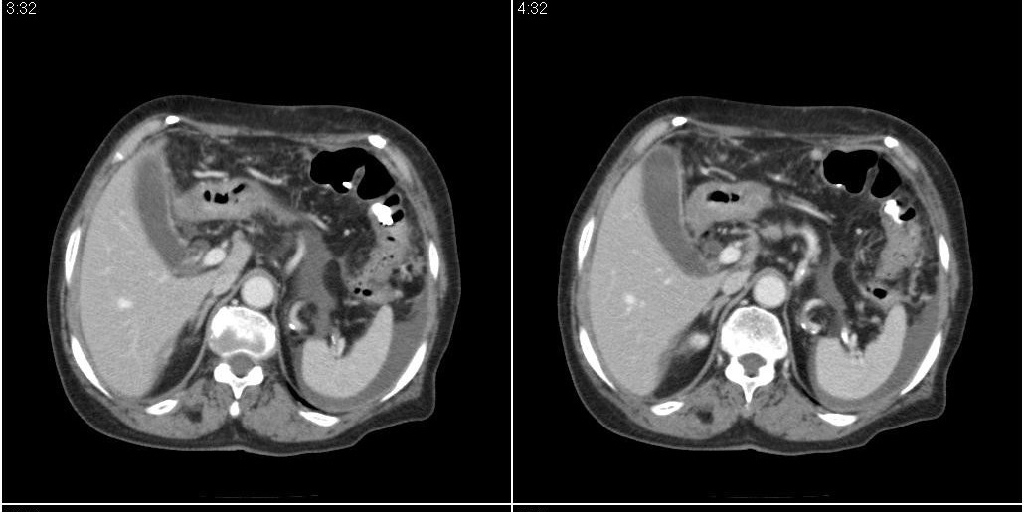

标题: CT24555:82岁女性,因为反复胸腹部积液进行CT检查,结果如下 [打印本页]

标题: CT24555:82岁女性,因为反复胸腹部积液进行CT检查,结果如下

胆囊有问题么,是结石么?胆囊内异常密度平扫30hu左右,增强各期无变化。

胆囊内稍高密度影,无强化,胆囊壁增厚,周围见低密度影,右侧膈肌角及脾周水样密度,支持胆囊泥沙样结石,胆囊炎、胆囊窝积液,胸腹水。